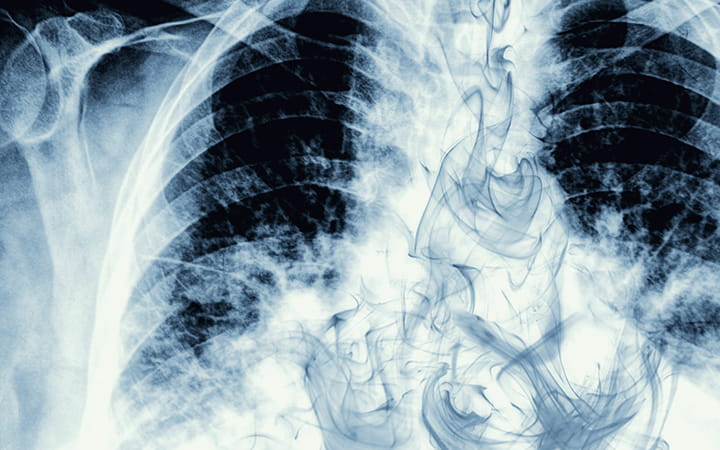

Vaping May Be More Dangerous Than Cigarette Smoking, Studies Show

Some people take up vaping – or inhaling vapor from electronic cigarettes – to avoid the health hazards of smoking cigarettes made with tobacco. But when it comes to your heart health, a pair of recent studies show e-cigarettes are just as dangerous – and possibly are even more dangerous – than traditional cigarettes.

There already is a clear connection between e-cigarettes and a lung condition called E-cigarette or Vaping Product Use-Associated Lung Injury (EVALI), Dr. Cireddu says.